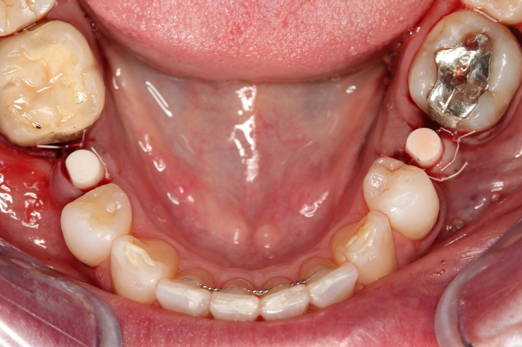

Figure 10 through Figure 13 show the preoperative x-ray and the sequence of beginning with healed sites through the surgical placement of the implants. The implants were protected by an Essix-style wound-protection removable retainer for approximately 12 weeks. After the integration phase, the implants and the natural dentition were prepared using traditional crown-and-bridge high-speed diamond and zirconia cutting burs to remove decay and existing restorative materials, to complete and refine the natural-tooth structures to receive full-crown coverage, and to prepare and refine gingival margins of the zirconia implants where needed.

After the preparations were evaluated and accepted by the clinician, provisionals were completed with traditional crown-and-bridge techniques. Then the provisionals were fabricated with a replication stent derived from the diagnostic wax up (Figure 14). The provisionals were well-fitted to both the natural dentition and the ceramic dental implants (Figure 15). The provisional that was fixed to the implant was kept out of occlusion and had a narrow buccal-lingual occlusal table. The smaller occlusal table and short occlusal scheme provided light loading forces and stimulated the bone tissuethe brain detects the stimuli and sends osteoblasts to the area to increase bone density surrounding the implant. The recommendation for the light-loading provisional phase was to have the patient function with the provisionals for 4 weeks.

Fig 12. Ceramic implants placed and sutured.

Figure 12

Fig 13. Lateral view after placement.

Figure 13

Fig 14. Final impression and cast.

Figure 14

Fig 15. Provisionals 12 weeks postoperatively.

Figure 15